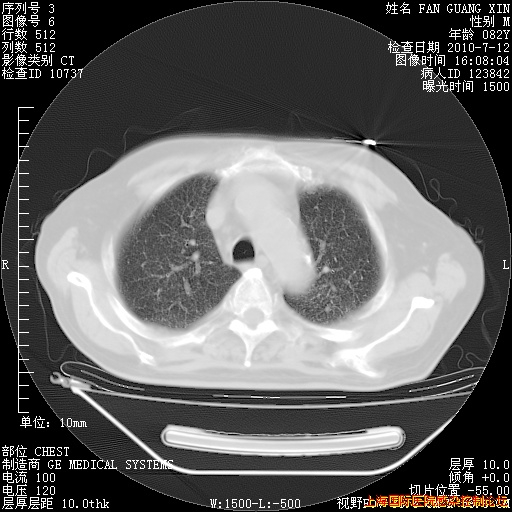

今天复查CT

今天CT

整整相隔30天的肺部CT好像有所好转啊。甲强龙减量第3天,需要观察体温。

海管,自昨日你和我通完话后,不知您岳父消化道症状有无缓解?体温怎样?阅读7.12日胸部ct,个人认为目前激素治疗是有效的,甲强龙减量是适宜的。因在抗痨治疗,需密切观察肝功、肾功能和血常规。不过,老年、长期住院和大量使用激素,很担心菌群失调发生